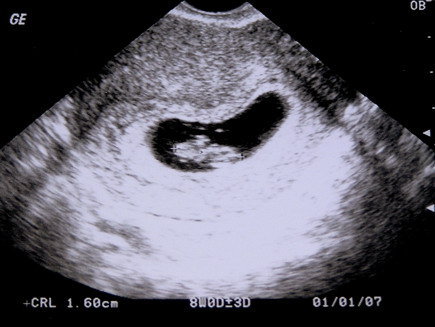

Na jo megcsinaltam :D , de mint mondtam nem tul eles... Felteszem az elso es a masodik UH kepet is.

Elso:

Kép

Masodik: